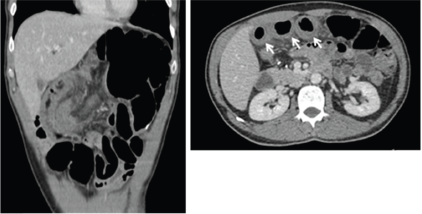

Regarding patients who were hospitalised due to severe enterocolitis (N = 8), the median age was 68.5 years (range: 50–77 years), four (50%) were older than 70 years (Table 2). Five patients were females, and seven patients had baseline performance status ECOG 0. Primary surgery was right colectomy in six (75%) and rectosigmoidectomy in two (25%). No patient had a protective ostomy. The median time between surgery and the first cycle was 45 days (95% CI: 42.4–47.5). Six patients were admitted after cycles 1 (3 pts) and 2 (3 pts), one patient after cycle 3 and one after cycle 5. The median length of hospitalisation was 15 days (range: 8–119 days). None of the patients presented with severe myelotoxicity or alopecia upon admission. All patients received antibiotics, mainly quinolones and metronidazole. Three patients were admitted to the intensive-care unit. No deaths occurred. During admission, seven patients underwent abdominal computed tomography (CT) scan. The main findings were wall thickening, dilated bowel and air-fluid levels, as shown in Figure 1. The most frequent segment affected was the ileum. After discharge from the hospital, three patients were switched to FOLFOX and one patient re-started CAPOX.

Figure 1. CT scan showing bowel thickening and dilation. Arrow shows small bowel thickening.